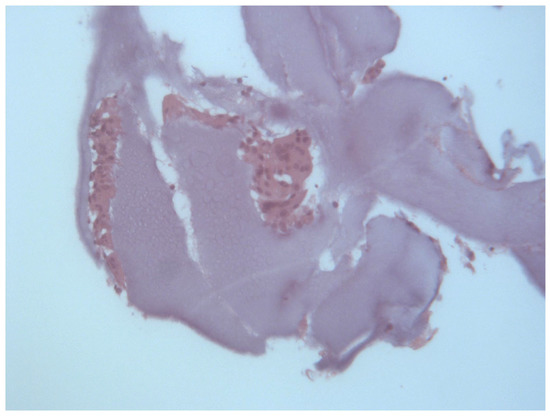

2.2. Histological Analysis

3.1. Histological and Clinical Follow-Up